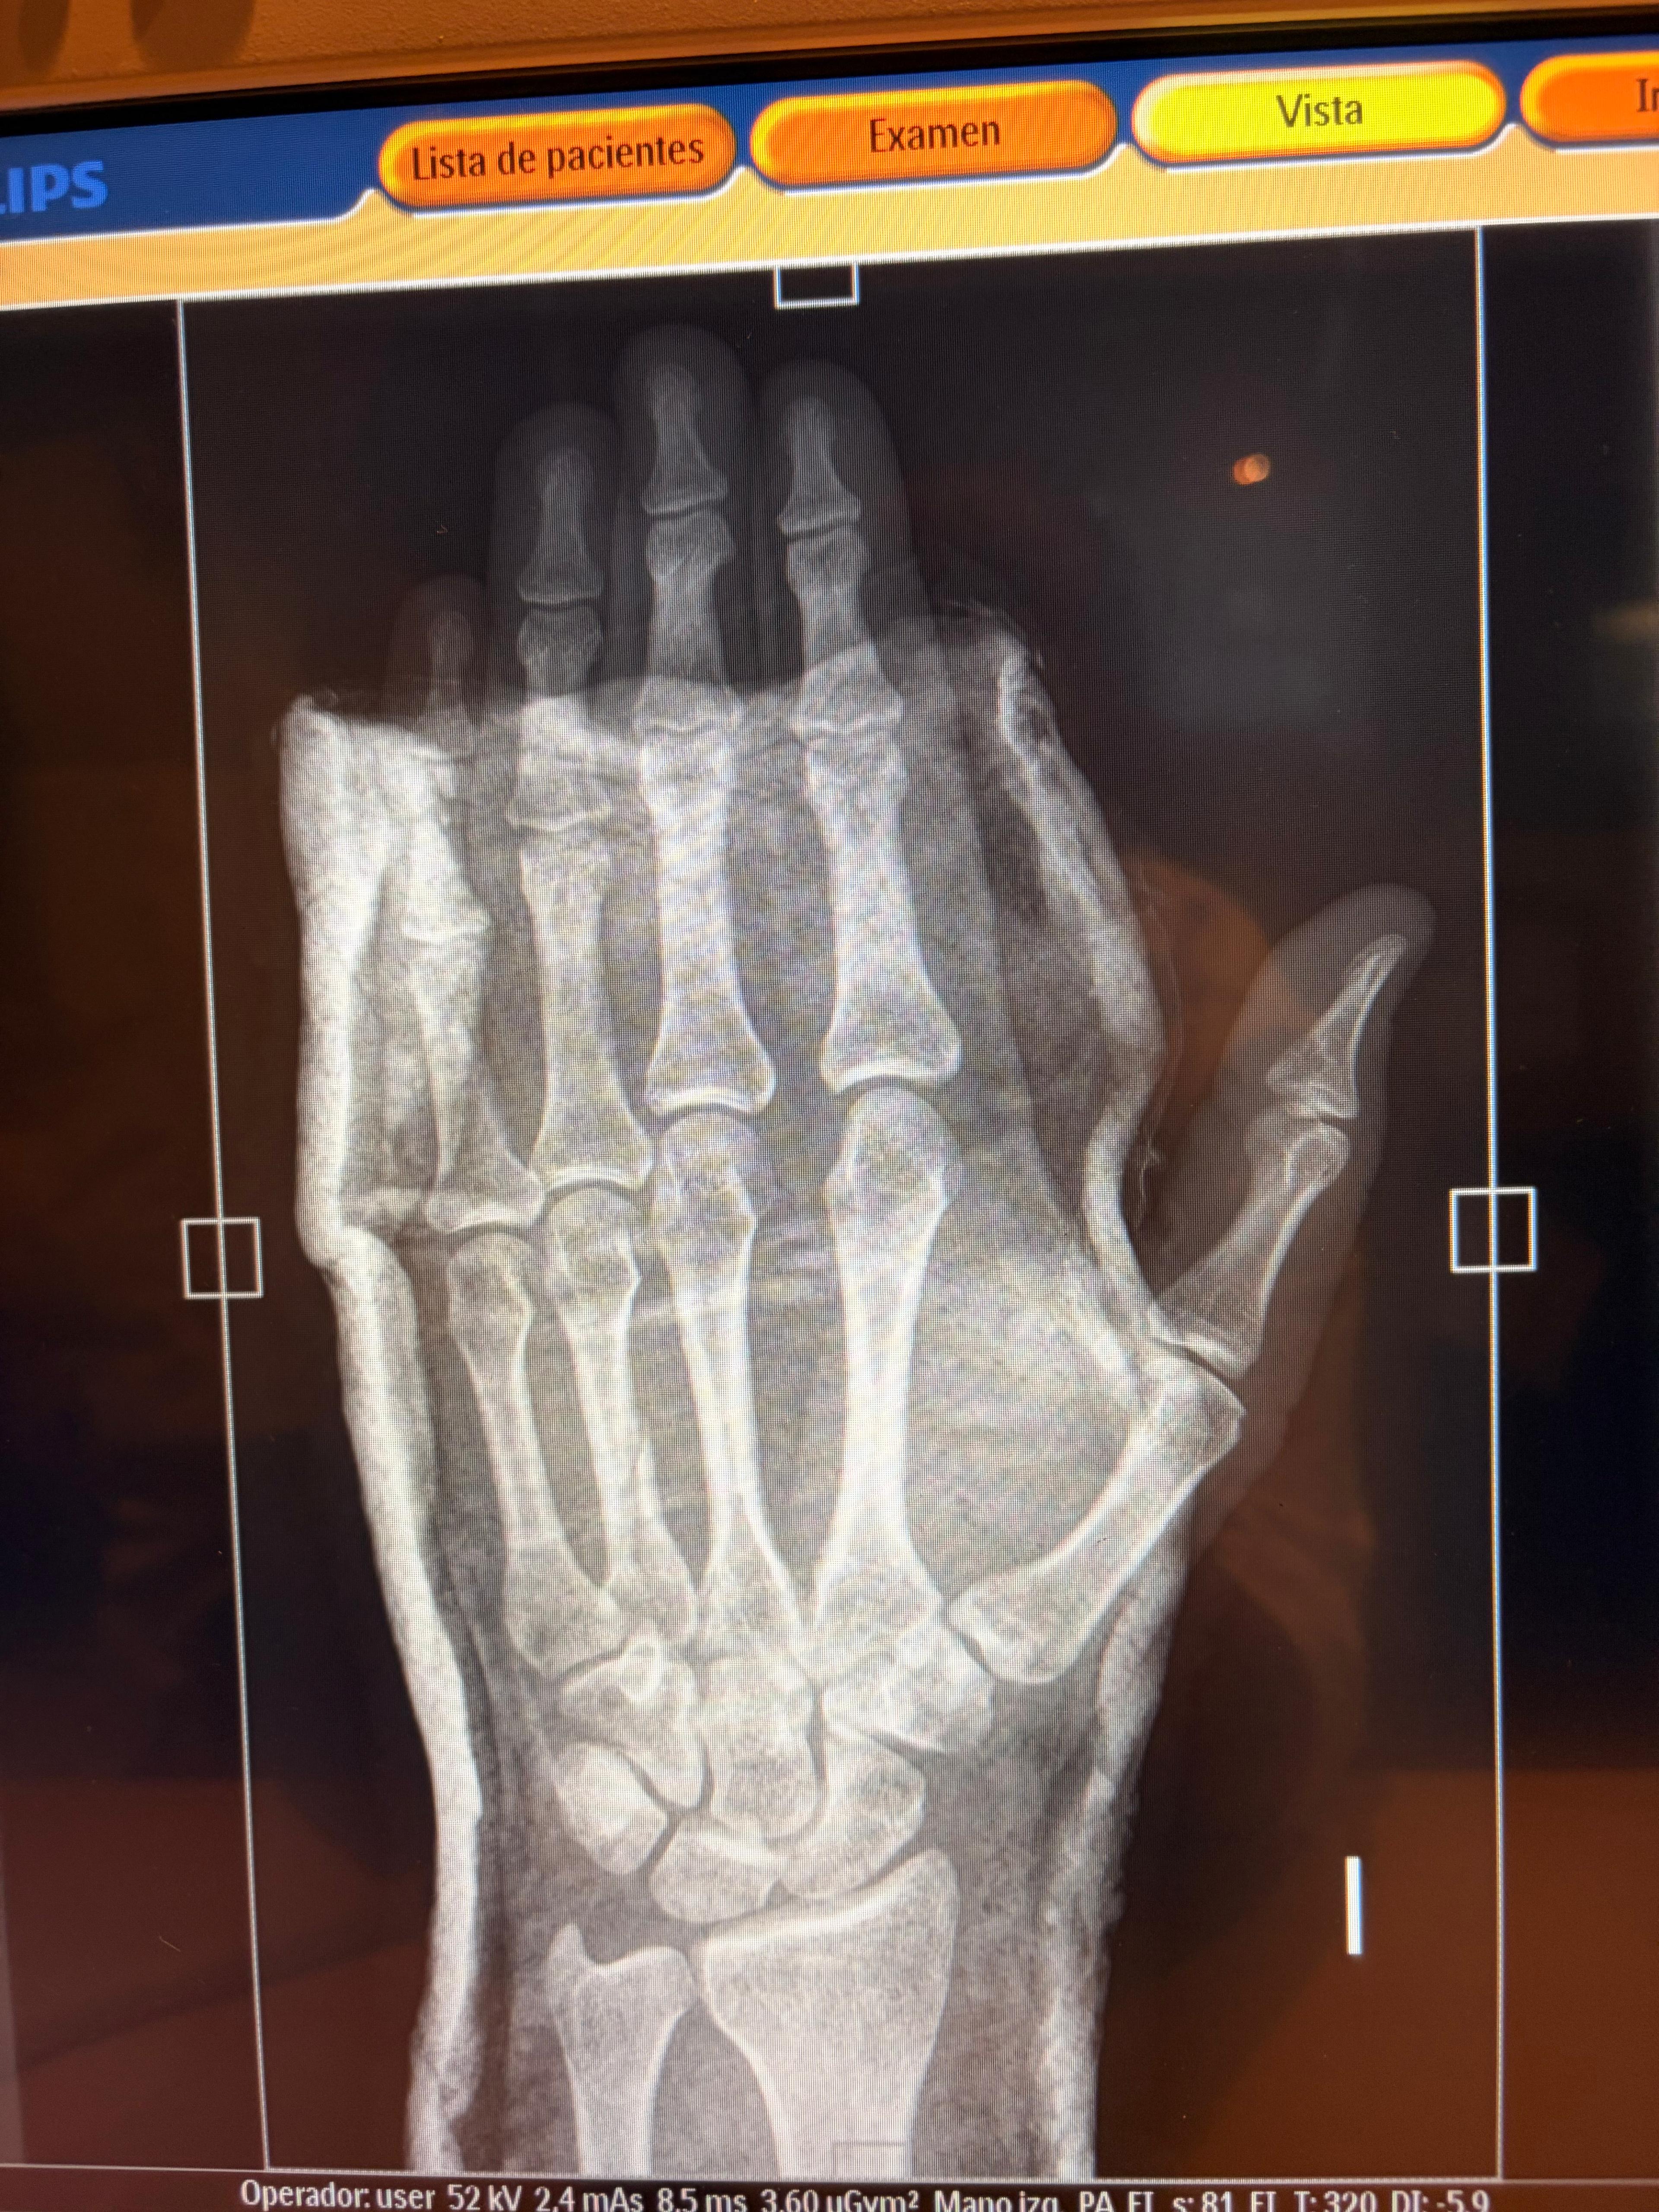

Fractura de falange producida por un anillo